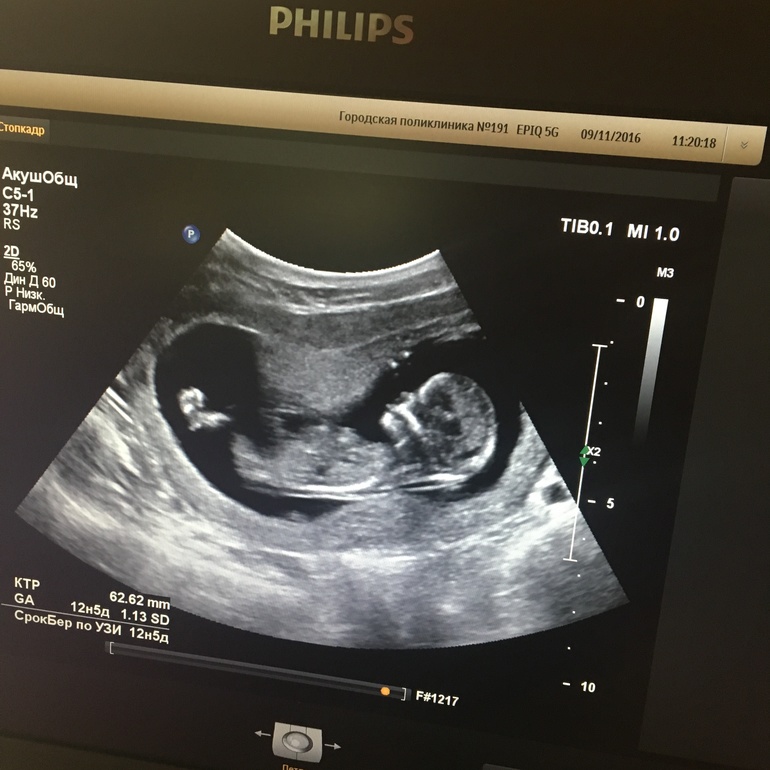

Новый житель моего живота))). Все на месте, развивается строго по сроку, всего ему хватает. Лежит, лапками шевелит)))